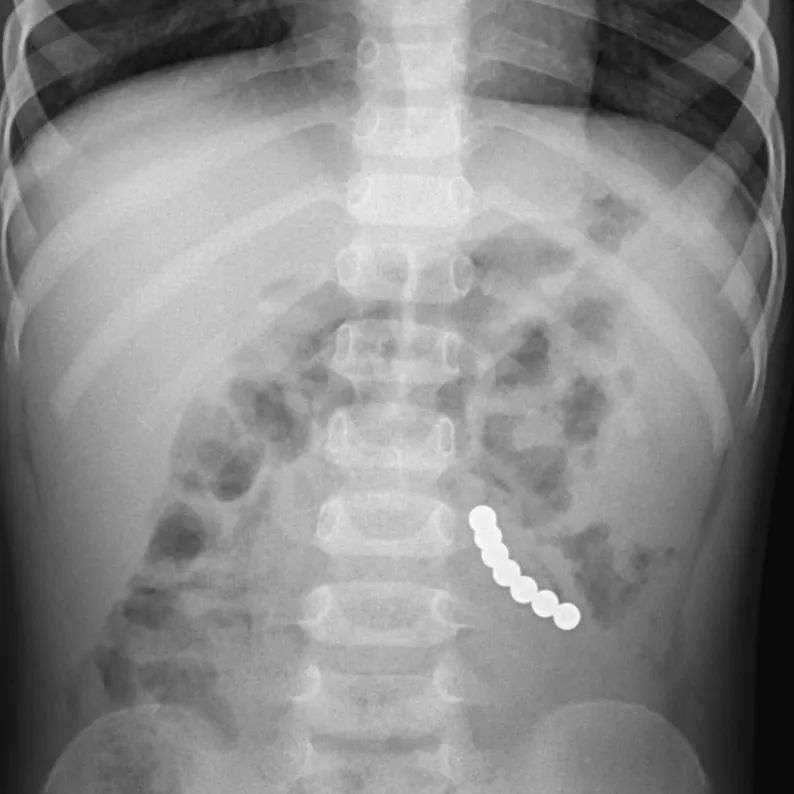

Untuk itu ayah bunda, selalu awasi anak balita saat bermain terutama dengan benda-benda kecil seperti magnet. Dokter Ariani Dewi Widodo, seorang spesialis anak, membagikan kasus anak yang menelan magnet bukan hanya satu tapi tujuh.

" Bulan Juli, Bunda menemukan si adik yang sebentar lagi 2 tahun sedang mengulum bola magnet itu. Fiuhh... untung sempat terlihat sebelum tertelan. Selanjutnya semua sudah melupakannya, hingga Oktober 2021 anak mulai mual muntah, kembung, dan nyeri perut berulang. Begitu difoto, tampak rangkaian 7 butir bola magnet yang saling berhimpitan. Rupanya yang ditemukan sebelumnya hanya sebagian saja, sudah ada yang terlanjur tertelan," tulis dr. Ariani.

Dokter Ariani memperingatkan jika anak setelah bermain benda kecil dan muntah-muntah apalagi sampai berwarna hijau, mengeluh sakit perut dan demam tinggi, segera konsultasi dengan dokter. Pemeriksaan rontgen dibutuhkan jika dicurigai anak anak menelan benda berbahaya.

Pada kasus yang ditangani dokter Ariani, anak tersebut awalnya bakal diberikan prosedur endeskopi untuk mengambil magnet, tetap letaknya terlalu jauh. Tak berhasil, akhirnya tim dokter memutuskan untuk melakukan operasi.

" Endoskopi dilakukan utk menariknya keluar, namun letaknya sangat jauh ke dalam. Jadi, dilanjutkan operasi oleh Dokter Bedah Anak handal Dr @cathlinefreya SpBA. Bola magnet tersangkut & menjepit jaringan usus. Ketujuh bola magnet berhasil dikeluarkan dengan sukses! Foto & post seizin orangtua & Humas @rsabhk demi kepentingan edukasi. Bersama kita saling mengingatkan dan menjaga," pesannya.